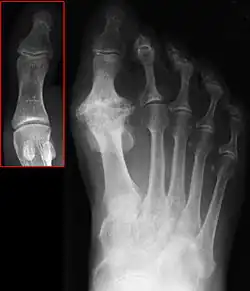

| Hallux not labeled but visible at upper left. | |

Hallux rigidus or stiff big toe is degenerative arthritis and stiffness due to bone spurs that affects the metatarsophalangeal joints (MTP) at the base of the hallux (big toe).

In 1988, Hattrup and Johnson described the following radiographic classification system:

- Grade I – mild changes with maintained joint space and minimal spurring.

- Grade II – moderate changes with narrowing of joint space, bony proliferation on the metatarsophalangeal head and phalanx and subchondral sclerosis or cyst.

- Grade III – severe changes with significant joint space narrowing, extensive bony proliferation and loose bodies or a dorsal ossicle.[3]